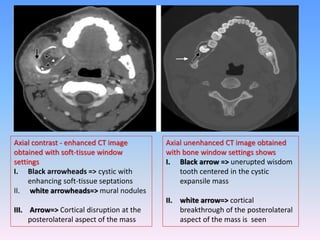

Axial contrast - enhanced CT image

obtained with soft-tissue window

settings

I. Black arrowheads => cystic with

enhancing soft-tissue septations

II. white arrowheads=> mural nodules

III. Arrow=> Cortical disruption at the

posterolateral aspect of the mass

Axial unenhanced CT image obtained

with bone window settings shows

I. Black arrow => unerupted wisdom

tooth centered in the cystic

expansile mass

II. white arrow=> cortical

breakthrough of the posterolateral

aspect of the mass is seen